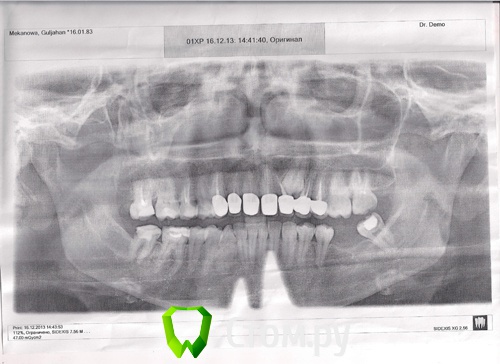

IvanK Опубликовано 17 декабря, 2013 Поделиться Опубликовано 17 декабря, 2013 Снимок плохого качества... он распечатан на бумаге? Попросите скинуть на флешку электронный вариант. 17, 15, 27, 47- перелечивать , с последующим протезированием коронкой.Консультация ортодонта,Протезирование с попрой на имплантаты 37,36, удаление 38 очень важно воссоздать контактные пункты между зубами. оценить коронки можно только при очной консультации у Врача Ортопеда.На снимке виден ретенированный клык.. Дискомфорт в области Ваших коронок может быть связан с плохим прилеганием коронок, клыком.. Ссылка на комментарий

red_butler Опубликовано 17 декабря, 2013 Поделиться Опубликовано 17 декабря, 2013 С поправкой на качество снимка - каких-либо серьезных пародонтальных проблем в области новых коронок я не вижу. Линкомицин больше не колите, Вас ведь не провязывают к креслу и насильно не колят. Когда увидем снимок надлежащего качества, можно будет судить о лечении корневых каналов. 1 Ссылка на комментарий

Jerena Опубликовано 17 декабря, 2013 Автор Поделиться Опубликовано 17 декабря, 2013 С поправкой на качество снимка - каких-либо серьезных пародонтальных проблем в области новых коронок я не вижу. Линкомицин больше не колите, Вас ведь не провязывают к креслу и насильно не колят. Когда увидем снимок надлежащего качества, можно будет судить о лечении корневых каналов.Я за нова сканировала с персом,попробуйте просмотреть Ссылка на комментарий